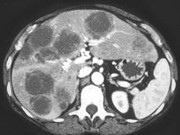

- 单项选择题男,54岁, 患者1年前行结肠癌手术,癌胚抗原增高, 影像检查如图,最可能的诊断为 ( )

A、肝淋巴瘤

B、多发结节性肝癌

C、多发性肝囊肿

D、多发性肝脓肿

E、结肠癌肝转移